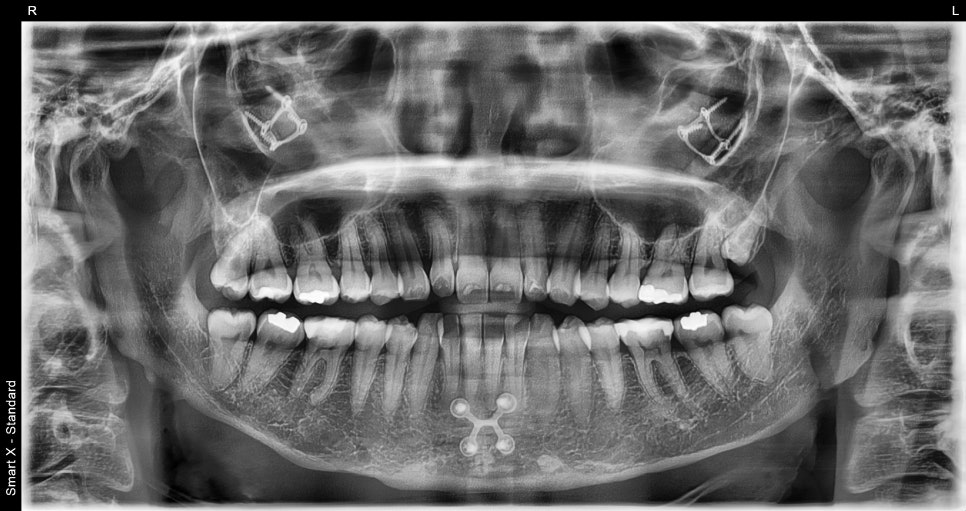

At Seoul Ob Dental Hospital,

intraoral photography

facial proportion analysis

analysis of tooth alignment and length

smile line design

are used to first establish the design that best suits the patient.

Through this process, laminates that blend well are created.